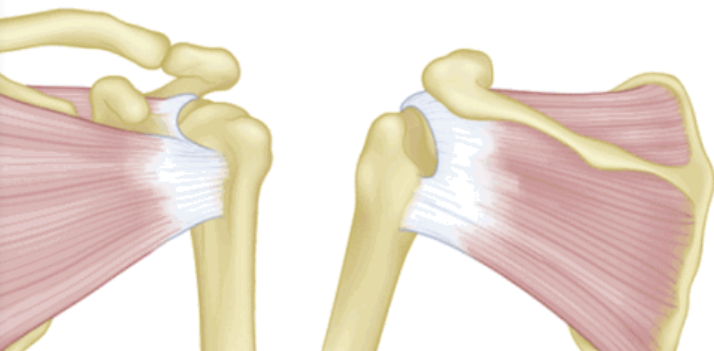

按照损伤程度分为部分撕裂( MR准确性>85% )和完全撕裂(MR准确性>95% )。

部分撕裂按照受损部位又分为滑囊面、关节面及肌腱内撕裂,在MRI上可以清晰的看到其受损部位。按照损伤深度分为1级:撕裂深度小于3mm,2级:撕裂深度在3-6mm,3级:撕裂深度大于6mm。

全层撕裂按照范围分为小撕裂:撕裂口<1cm,中撕裂:撕裂口1-3cm,大撕裂:撕裂口3-5cm,巨大撕裂:撕裂口>5cm。高清晰度的MRI是可以测定撕裂范围的。